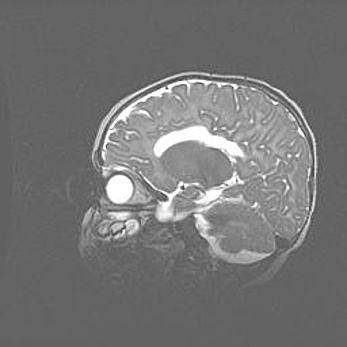

Мальформация Денди-Уокера. Киста задней черепной ямки.

Агенезия мозолистого тела.

Возраст: 2,5 месяца

Вес: 2420 г

Пол: женский

Окружность головы: 37 см

Срок гестации: 32 недели

Мальформация Денди—Уокера — редкий вид патологии ЦНС, представляющий собой врожденный порок развития каудального отдела ствола и червя мозжечка, ведущий к неполному раскрытию срединной (Мажанди) и латеральных (Лушка) апертур IV желудочка мозга. Для этогно синдрома характерна триада симптомов: гипотрофия червя мозжечка и/или полушарий мозжечка, кисты задней черепной ямки, гидроцефалия различной степени. В 70% случаев порок сочетается и с другими аномалиями головного мозга, в частности с агенезией мозолистого тела.